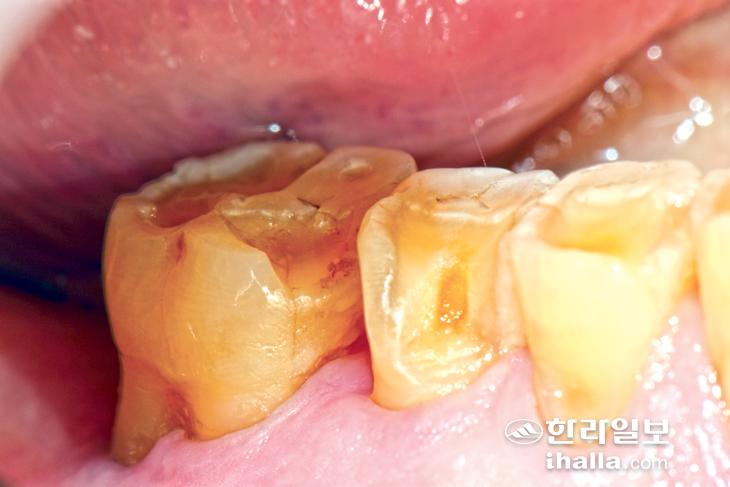

위의 사진은 34세 환자의 치아로 마모 정도의 차이를 확실히 파악할 수 있다.

91세 고령의 환자이기에 이런 경우는 노화에 따라 자연적으로 진행된 마모라고 할 수 있다. 하지만 40~50대 환자의 치아가 이러한 마모소견을 보인다면 비 기능이상습관이 있는 것으로 짐작해 볼 수 있다.